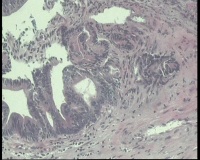

急!请老师帮忙看看,单位同事肠镜病理

进镜达横结肠近肝曲,见不规则增生性肿物,环周生长,表面充血糜烂,触之易出血,肠腔狭窄,镜身无法通过

肠镜活检4块

镜下腺体异型小,纤维间质反应,能直接报结肠腺癌吗?

可一类报告报:管状绒毛状腺癌

高-中分化腺癌。